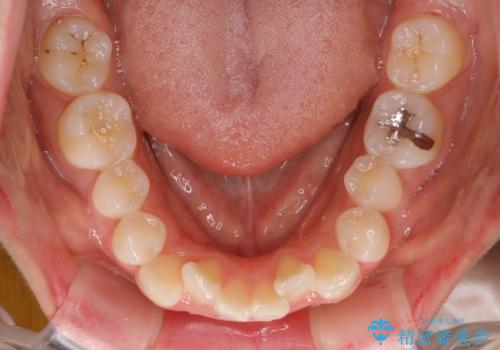

- 前歯のがたつきと出っ歯が気になるとのことで来院されました。

上顎の前から4番目の歯を両側合計2本抜歯して矯正することとなりました。

抜歯をして矯正をすることで、前歯を後方に移動させ、ガタガタを改善することができました。